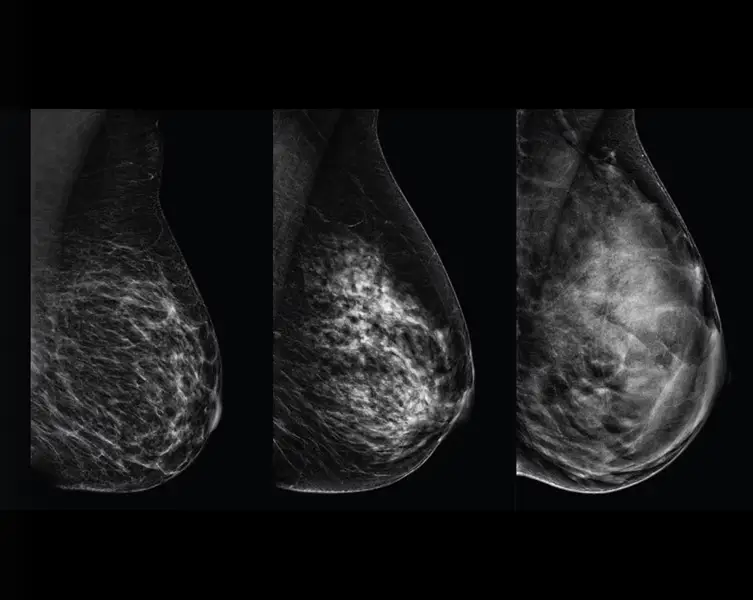

Zašto je gusto tkivo dojke važno

Gusto tkivo dojke i karcinom na mamografiji se prikazuju bijelo, što može prikriti male lezije. Zapravo, do 50% karcinoma dojke može ostati neotkriveno kod izrazito gustog tkiva dojke.⁴